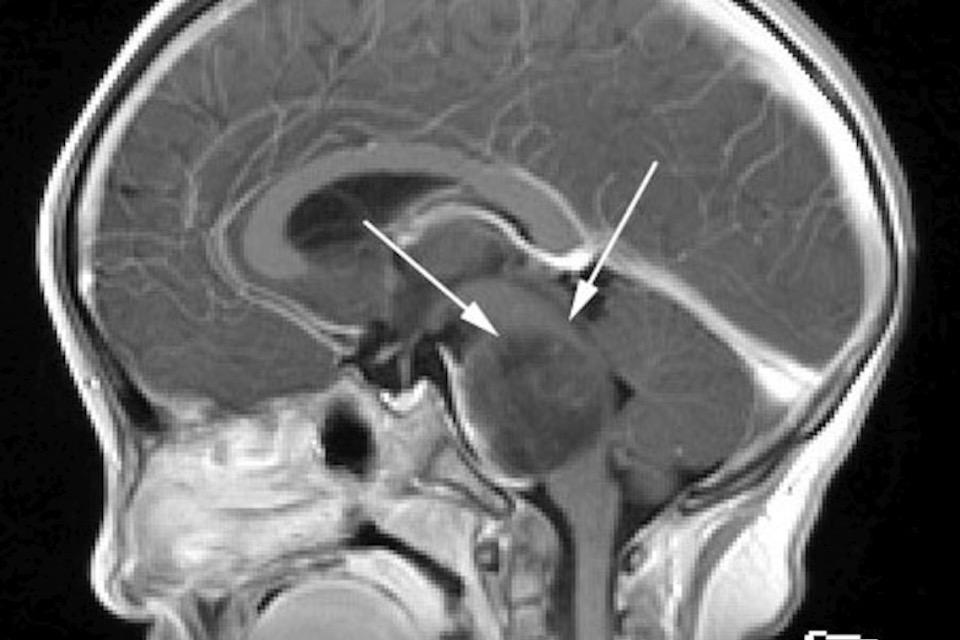

In particular, DIPG (Diffuse Intrinsic Pontine Glioma) is a treatment-resistant brain tumor that primarily affects children between the ages of six and eight.

DMG refers to Diffuse Midline Gliomas, a group of cancers characterized by H3 K27M gene mutations, typically occurring in the brainstem, thalamus, and spinal cord.DIPG stands for Diffuse Intrinsic Pontine Glioma, a tumor that develops within the pons, a part of the brainstem.Although numerous studies are currently underway around the world, no research has yet led to a cure.